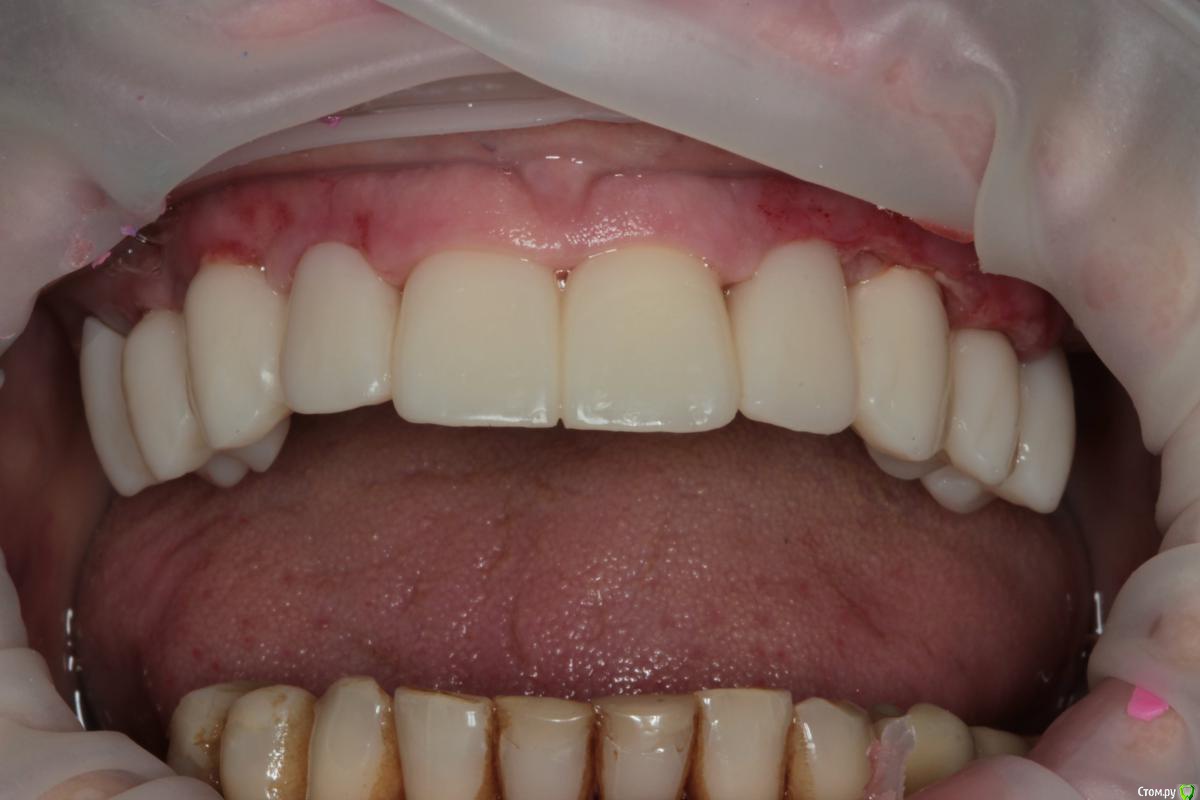

Популярный пост Abuk Опубликовано 24 ноября, 2015 Популярный пост Поделиться Опубликовано 24 ноября, 2015 Планировали 8 имплантатов.Буду рад конструктивной критике.Фото с мокап.Через 6 днейДалее хотели поставить 6 ки, она отказалась (не хотели синусы)и решили все по-другому .Через 2мес пришла с отколотыми консолями )Прошу прощения ,что ортопедию выложил не в том разделе), не хотел делить. 26 1 Ссылка на комментарий

Abuk Опубликовано 24 ноября, 2015 Автор Поделиться Опубликовано 24 ноября, 2015 (изменено) Радикально Вы. Что оставили ей после имплантации-это инд аббатменты? На них мокап одели и нагрузили сразу? У всех был торк хороший? Или это временные абб? Что за систему использовали? В планах консоль назад, правильно я понимаю?Спасибо.увидев такую работу,сам так же подумал бы). Но там подвижность 2-3 ст. ближе к 3. Мосты болтались ,2 ки в хлам. 1 ки только стабильны. Снимал мосты,проводил кюретаж. Решил дернуть.Абатманы временные, тех. сделал на них коронки. Система анкилоз. Работа,на посл. фото, постоянная . Имплы в области 4 и по одному моляру ,консоли. Мок ап был до имплантации . По нему шаблон. Стабильность 15 -20 на 23 , остальное больше 30. Изменено 24 ноября, 2015 пользователем Abuk 1 Ссылка на комментарий

Abuk Опубликовано 24 ноября, 2015 Автор Поделиться Опубликовано 24 ноября, 2015 Вы лунки тоже аугментиовали?Хирургия понравиласьДа, спасибо. Если не сложно, напишите что вам не понравилось в ортопедии.Техничка мне самому не очень , хотя многим ,включая пациента, понравилась Ссылка на комментарий